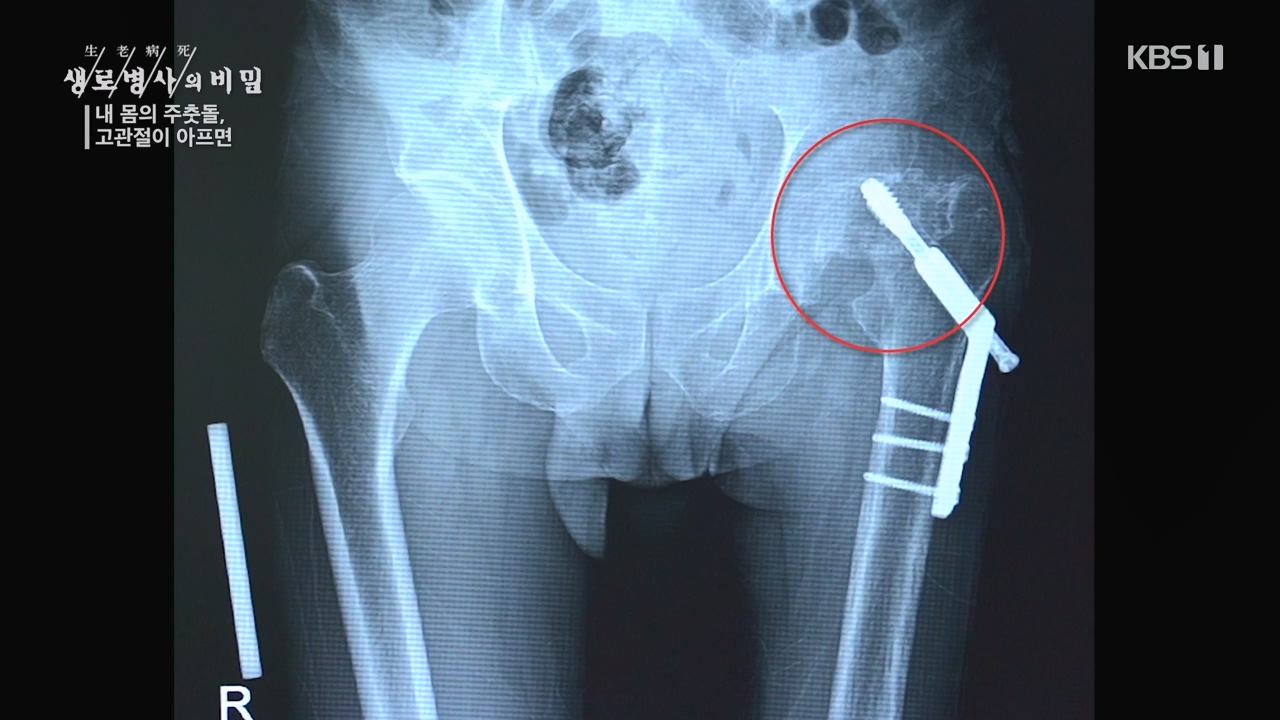

[박은철 기자] 앉고 서고 걷고 달리는 등 우리가 움직이는 순간마다 쉼 없이 일하는 관절이 있다. 엉덩이 관절이라고도 불리는 '고관절'은 상체와...